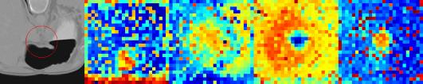

Evaluating lesion progression and treatment response via longitudinal lesion tracking plays a critical role in clinical practice. Automated approaches for this task are motivated by prohibitive labor costs and time consumption when lesion matching is done manually. Previous methods typically lack the integration of local and global information. In this work, we propose a transformer-based approach, termed Transformer Lesion Tracker (TLT). Specifically, we design a Cross Attention-based Transformer (CAT) to capture and combine both global and local information to enhance feature extraction. We also develop a Registration-based Anatomical Attention Module (RAAM) to introduce anatomical information to CAT so that it can focus on useful feature knowledge. A Sparse Selection Strategy (SSS) is presented for selecting features and reducing memory footprint in Transformer training. In addition, we use a global regression to further improve model performance. We conduct experiments on a public dataset to show the superiority of our method and find that our model performance has improved the average Euclidean center error by at least 14.3% (6mm vs. 7mm) compared with the state-of-the-art (SOTA). Code is available at https://github.com/TangWen920812/TLT.